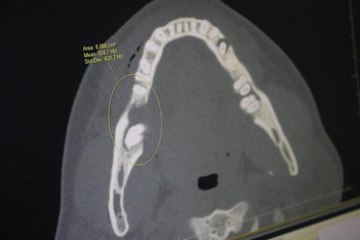

Barış Çakmaklı’nın ağız içerisinde tespit edilen kötü huylu tümörle birlikte çenesinin bir kısmı alındıktan sonra yerine kaval kemiğinden parça kesilerek eksik kısım tamamlandı.